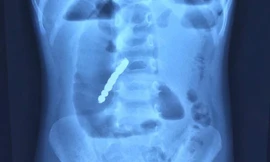

TPO - Nhập viện trong tình trạng đau bụng, nôn ói, bí đại tiện, bệnh nhi được bác sĩ kiểm tra hình ảnh thì phát hiện trong đường tiêu hóa có nhiều dị vật cản quang. Các bác sĩ đã tiến hành phẫu thuật lấy ra 20 viên nam châm và cắt bỏ đoạn ruột bị hoại tử.

TPO - Nhập viện trong tình trạng đau bụng quằn quại, bệnh nhi được bác sĩ kiểm tra phát hiện trong đường tiêu hóa có nhiều dị vật xếp thành hình vòng tròn. Trong quá trình phẫu thuật lấy dị vật, bác sĩ phát hiện 14 viên nam châm hít vào nhau đã khiến bệnh nhi bị thủng ruột.

TPO - Được bạn cùng lớp cho 5 viên bi nam châm nhưng sợ bị cô phát hiện, tịch thu, bé gái 6 tuổi ngậm vào miệng để giấu. Tuy nhiên, trong lúc sơ ý, cháu đã nuốt cả 5 viên bi vào dạ dày và phải nhập viện cấp cứu.

TPO - Trẻ ngậm trong miệng rồi nuốt lúc nào không biết, đến khi đau đớn quằn quại phải nhập viện thì đã bị thủng ruột bởi 2 viên bi nam châm gây ra. Bác sĩ cảnh báo, nuốt dị vật là tai nạn rất nguy hiểm có thể cướp đi sinh mạng của bệnh nhi.

TPO - Nhân dịp sinh nhật, bé gái được mẹ mua cho một bộ đồ chơi có nhiều viên bi nam châm. Trong lúc chơi đùa, bé đã vô tình nuốt phải 4 viên bi khiến ruột bị tắc, nguy kịch đến tính mạng.